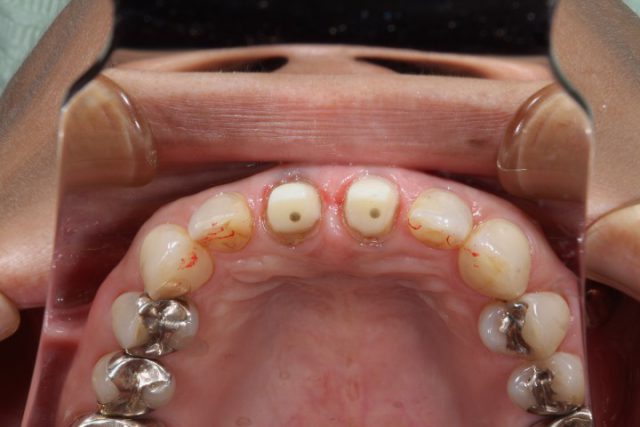

施術中

施術中です。オールセラミックをかぶせるための土台を形成しています。